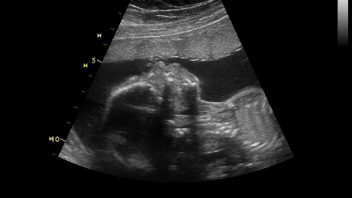

Tatínku a já tě kopnu!

KLUB TĚHULEK! LUCIE Tento týden byl odpočinkový, polehávací a regenerovací. Byla jsem hrozně unavená a celkově vyčerpaná z pobytu v nemocnici a celé té virozy, co jsem chytla, ještě jako bonus jsem si z nemocnice dovezla rýmu, takže jsem byla vyřízená. V noci už pořádně nespím, skoro hodinu co hodinu se budím a chodím buď na záchod nebo se obracím na druhý bok, protože se mi špatně leží. Pak to doháním druhý den, občas si schrupnu po obědě. Fakt jsem ráda, že nechodím do práce, asi bych toho nebyla schopná ještě dělat nějaké pracovní výkony.